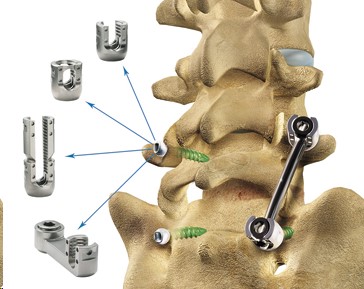

Firebird Deformity Correction System

Firebird NXG Spinal Fixation System

FIREBIRD Spinal Fixation System